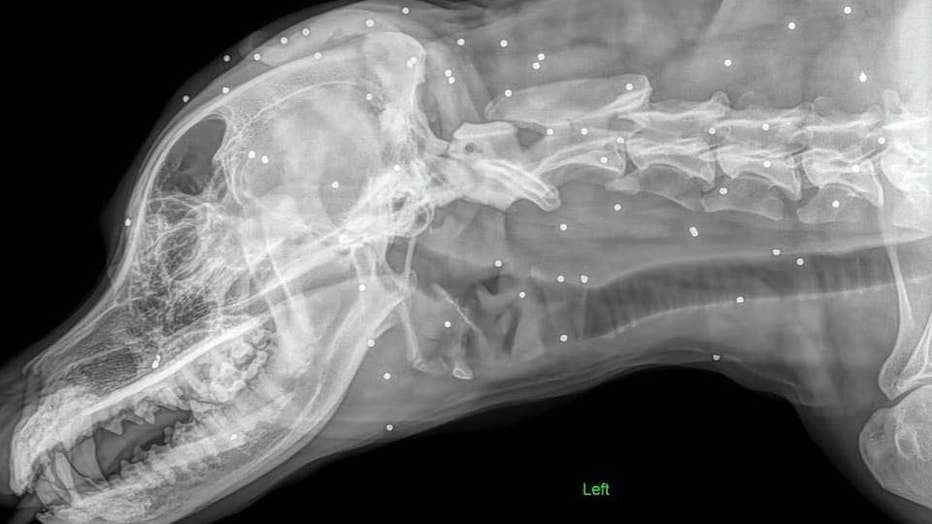

Sadly, Poodle and Pooch Rescue of Florida says the adorable dog came to them with nearly 100 pellets embedded in his body.

"Teddy came into a local shelter with a head and neck full of buckshot/pellets/bb’s and they asked for our help," the rescue wrote on Facebook. "Sadly, he’s likely lived with them a while as he doesn’t have any open wounds."

The rescue posted photos of Teddy to Facebook, with an X-ray showing pellets all over this body.

"The shelter thought he showed signs of arthritis which is why the rads were taken and they found the pellets in his face, head, neck, shoulders, and legs."